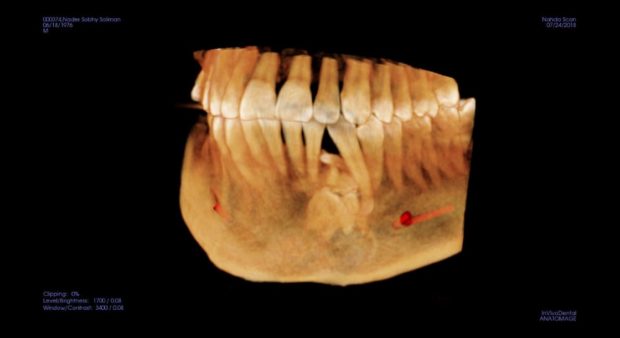

اكتب تجربتي الشخصية هذه شهادة حق لهذا الإنسان الأستاذ الدكتور محمد المفتي استاذ جراحة اللثة و الفم و الوجة و الفكين. دكتور محمد المفتي هو نجل عالم جليل في جراحة الوجة و الفكين الأستاذ الدكتور شريف المفتي رحمة الله عليه و اعرفه معرفة شخصية و تقابلت معه بالعيادة في المهندسين بعام ٢٠١١ و ٢٠١٢ للكشف و في الحقيقة ذهبت في ٢٠١٨ شهر يناير الماضي للكشف في نفس العيادة و لكن علمت أن توفاة الله و موجود نجلة الأستاذ الدكتور محمد المفتي استاذ بجامعة عين شمس كلية طب الأسنان و فعلا كما قالوا في الامثال ” اللي خلف مامتش” قام دكتور محمد المفتي بفحص الفم واللسان و الشفاة و الأسنان و اللثة و الفكين للتأكد من عدم وجود أي شيء غير طبيعي و انا في الحقيقة بطبعي قلوق جدا . طلب منى اشعة بانوراما عادية علي الفكين و عملتها و تم عرضها علية فعاد و طلب مقطعية للتأكد من شيء موجود تحت الناب الايسر بالفك السفلي و بالفعل عملت المقطعية و تم عرضها علية و قالي هنتابعها هى حاجة عندك من سنين طويلة يمكن اكتر من ٢٠ سنة و موجودة في اشعات البانوراما القديمة اللي كنت بتعرضها علي دكتور شريف المفتي في ٢٠١١ و ٢٠١٢ رحمة الله علية هى اسمها compound odontoma و حاجة حميدة تماما و لا خوف منها و ممكن تعيش بيها لكن هنتابع حجمها بالمقطعية كل ٦ شهور و متقلقش منها .

المهم انا ابتديت اقلق و لفيت علي دكاترة مشهورة بالقاهرة بدون ذكر اسماء منهم من جعل حياتي جحيم حتي اليوم الوسواس القهرى يطاردني من كلامهم الذي حتي الان لا يفارق أذني منهم من قال لي عملية و فورا و لازم نستأصل الورم بسرعة و احتمال كمان نستأصل معاة جزء من الفك و تحليل العينة لإثبات كونة خبيث ام حميد. ! قلبي هيقف من الكلام و لا اكل ولا نوم و لا راحة ..! الغريب أن انا اتصلت علي دكتور محمد المفتي و قولتلة بدون ذكر الاسم ان فية دكتور قالي كذا علي الفور دكتور المفتي ضحك و قالي انت روحت عند الجزار! قولتلة مين ! قالى فولان و قالك كمان العملية هتتكلف كذا قولتلة صح حصل ! قالي انت لو عاوز تعملها اعملهالك و مش عاوز منك فلوس لكن انا بقولك دى مجموعة اسنان زيادة مطلعوش من وانت صغير لان اسنانك كانت كاملة حوالي ٦ او ٧ تحت الناب و حجمهم تقريبا ٢ سم و قولنا نتابعها فقط بالمقطعية مش واثق فيا شوف حد تاني و بالفعل قالي روح لدكتور فولان انسان محترم و اعرض علية الموضوع عشان ترتاح و ابقي بلغني قالك اية بالفعل روحت و تم عرض كل شيء علية قالي نصا تنساها تماما و تعيش حياتك انا هاخد منك فلوس و اشتغل بس حرام عليا مش محتاجها و كتبلي تقرير قولتلة طيب نتابعها كل ٣ شهور و لا ٦ شهور عشان ممكن تكبر او تتحول لخبيث قالي مش بتتحول مستحيل و لا تعمل مقطعية تاني و لو عملت بعد سنتين هتلاقي الحجم دا زى ما هو دى حاجة بتكبر ببطىء شديد جدا علي مدار سنين طويلة جدا . المهم رجعت للدكتور محمد المفتي قالي ها صدقت !! بس معلش هنعمل مقطعية بعد ٦ شهور قولتلة حاضر . من حرق دمى دخلت علي الواتس للدكتور اللي قالي لازم نستأصل بسرعة و قولتلة شوف كدا الإشاعات القديمة دى من ٢٠١١ و ٢٠١٢ قالي مش فاضي كلمني الصبح قولتلة انت دكتور عار علي مهنة الطب و عار علي الإنسانية و تاني يوم اتصلت بية و غير كلامة تماما و قالي مافيهاش حاجة و حاجة حميدة ممكن تتعايش معاها بس الخوف ليحصل اي خبطة في الفك ينكسر! رجعت للدكتور المفتي قولتلة الكلام دا قالي ولا هيتكسر و لا هيحصلة اي حاجة . و كان دايما يقولي ربنا حلو اوى انت انسان قريب من الكنيسة عندكم آباء رائعين و انت بتعرف البابا نفسة و كل الأساقفة الناس دى هتخلى عندك قوة روحية عالية . و عاوز اقول ان دكتور محمد المفتي بيرفض حتي ياخد مني الكشف و اي وقت ارن علية اشكيلة من اي حاجة او تطور يقولي متنزلش مخصوص القاهرة صور اللي تاعبك صور كويسة واضحة سواء لسان لثة اسنان و ابعتلي علي الواتس و ارجع اتصل بية يرد عليا و يطمني و يقولي كلة طبيعي. انت نفسيتك تعبانة يا باشمهندس حد ضايقك الفترة دى ! حصل حاجة مضيقاك و افضفض معاة … بصراحة الراجل دا اتحملني فوق الوصف و اخيرا عدى ٦ شهور و ذهبت اعمل تنظيف الأسنان بعدها تعبت جدا و ندمت اني نظفت اللثة التهبت و مازالت تعباني بعد التنظيف .. قولت اعمل اشعة بانوراما مع نفسي كدا اطمن علي المشكلة.. لقيت الحجم شكلو متغير عن اللي فاتو بتوع ٢٠١٨ و ٢٠١١ و ٢٠١٢ بعتها لدكتور محمد المفتي واتس و اتصلت علية .. قالي مالك مال صوتك مخنوق ! قولتلة انا ملاحظ تغيير قالي نعمل مقطعية قولتلة فين قالي مضطر تنزل القاهرة كدا و بعدين سكت شوية و هو عارف ظروف ماما تعبانة بجلطة و مفيش غيري معاها.. قالي اسمع قولتلة نعم قالي جامعة النهضة بني سويف قريبة منك؟ قولتلة طبعا قالي انا هكون موجود هناك غدا بكلية طب الأسنان تعالي و هنعمل مقطعية عندنا و بالفعل روحت قالي اسمع البانوراما دى بايظة و مش هيطلع اي تغير قولتلو لاء يا دكتور انا ملاحظ الاشعة و الفرق قالي ماشي يا فندم بينا المقطعية!

و من قلقي كل شوية اتصل علية و الراجل يرد و يشرح و يشرح و انا منتظر المقطعية لحد ما عملت المقطعية من يومين و تركت ال cd للدكتور محمد المفتي لان وجدتة في اجتماع مع رئيس جامعة النهضة بني سويف و اول مرة كنت اعرف من الناس اللي في الجامعة ان دكتور محمد المفتي يبقي وكيل كلية طب الأسنان جامعة النهضة بني سويف و ايضا استاذ دكتور بجامعة عين شمس القاهرة مكان تواجدة.

و بعد عرض ال cd قومت بالاتصال علية قالي مافيش اي تغير يا نادر زى ماهي و مافيش حاجة تخوفني.